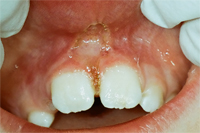

Die Abb. 1 bis 4 sollen als anschauliche Beispiele für gesunde und kranke Fundamente dienen.

Der Erfolg der Behandlung ist deutlich in den Abb. 2 und 4 zu sehen. Sehr augenfällig konnte die Situation um den Eckzahn im linken Oberkiefer verbessert werden (vergleiche dazu Abb. 3 vorher und Abb. 4 nachher).